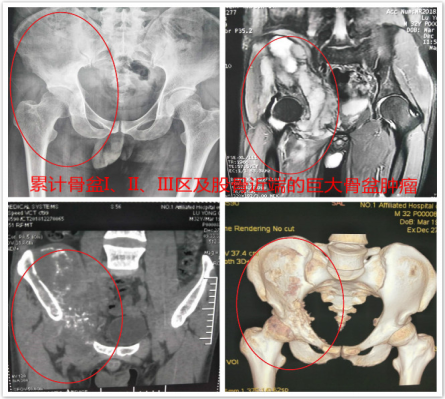

日前,骨病骨肿瘤科在多学科协作性,成功完成 “骨盆I+Ⅱ+Ⅲ区巨大骨肉瘤腹主动脉球囊阻断下完整半骨盆肿瘤切除+腰骶椎骨盆重建+髋关节置换术 ”1例。

患者33岁男性,髋部疼痛不适3月余入院,经检查及病理提示骨盆I+Ⅱ+Ⅲ区巨大恶性骨肿瘤。骨盆的恶性肿瘤,往往就诊时肿瘤已经发展了相当长的时间,而肿瘤巨大、术中出血多、局部解剖结构复杂等因素使得手术难度及风险增高。早年对骨盆恶性肿瘤的治疗,半骨盆截肢术是骨盆恶性肿瘤的主要治疗方式。但患者所承受的心理压力巨大,面对肢体残缺所引起的恐慌使其拒绝接受治疗,尤其对于年轻患者。保肢术的开展及应用为这些患者带来希望,但手术难度极大,不易达到安全的外科边界。胡勇教授团队根据患者病情,制定精细手术方案,多套治疗及手术预案,于我科行3次化疗,缩小肿瘤反应区。积极完善术前准备工作后于患者行骨盆I+Ⅱ+Ⅲ区巨大骨肉瘤行腹主动脉球囊阻断+半骨盆肿瘤切除+腰骶椎骨盆重建+髋关节置换术,术中既完整切除了巨大骨盆肿瘤,又重建了腰骶椎及骨盆、髋臼的稳定性,最大程度的保留肢体功能,患者术后恢复良好,顺利出院。